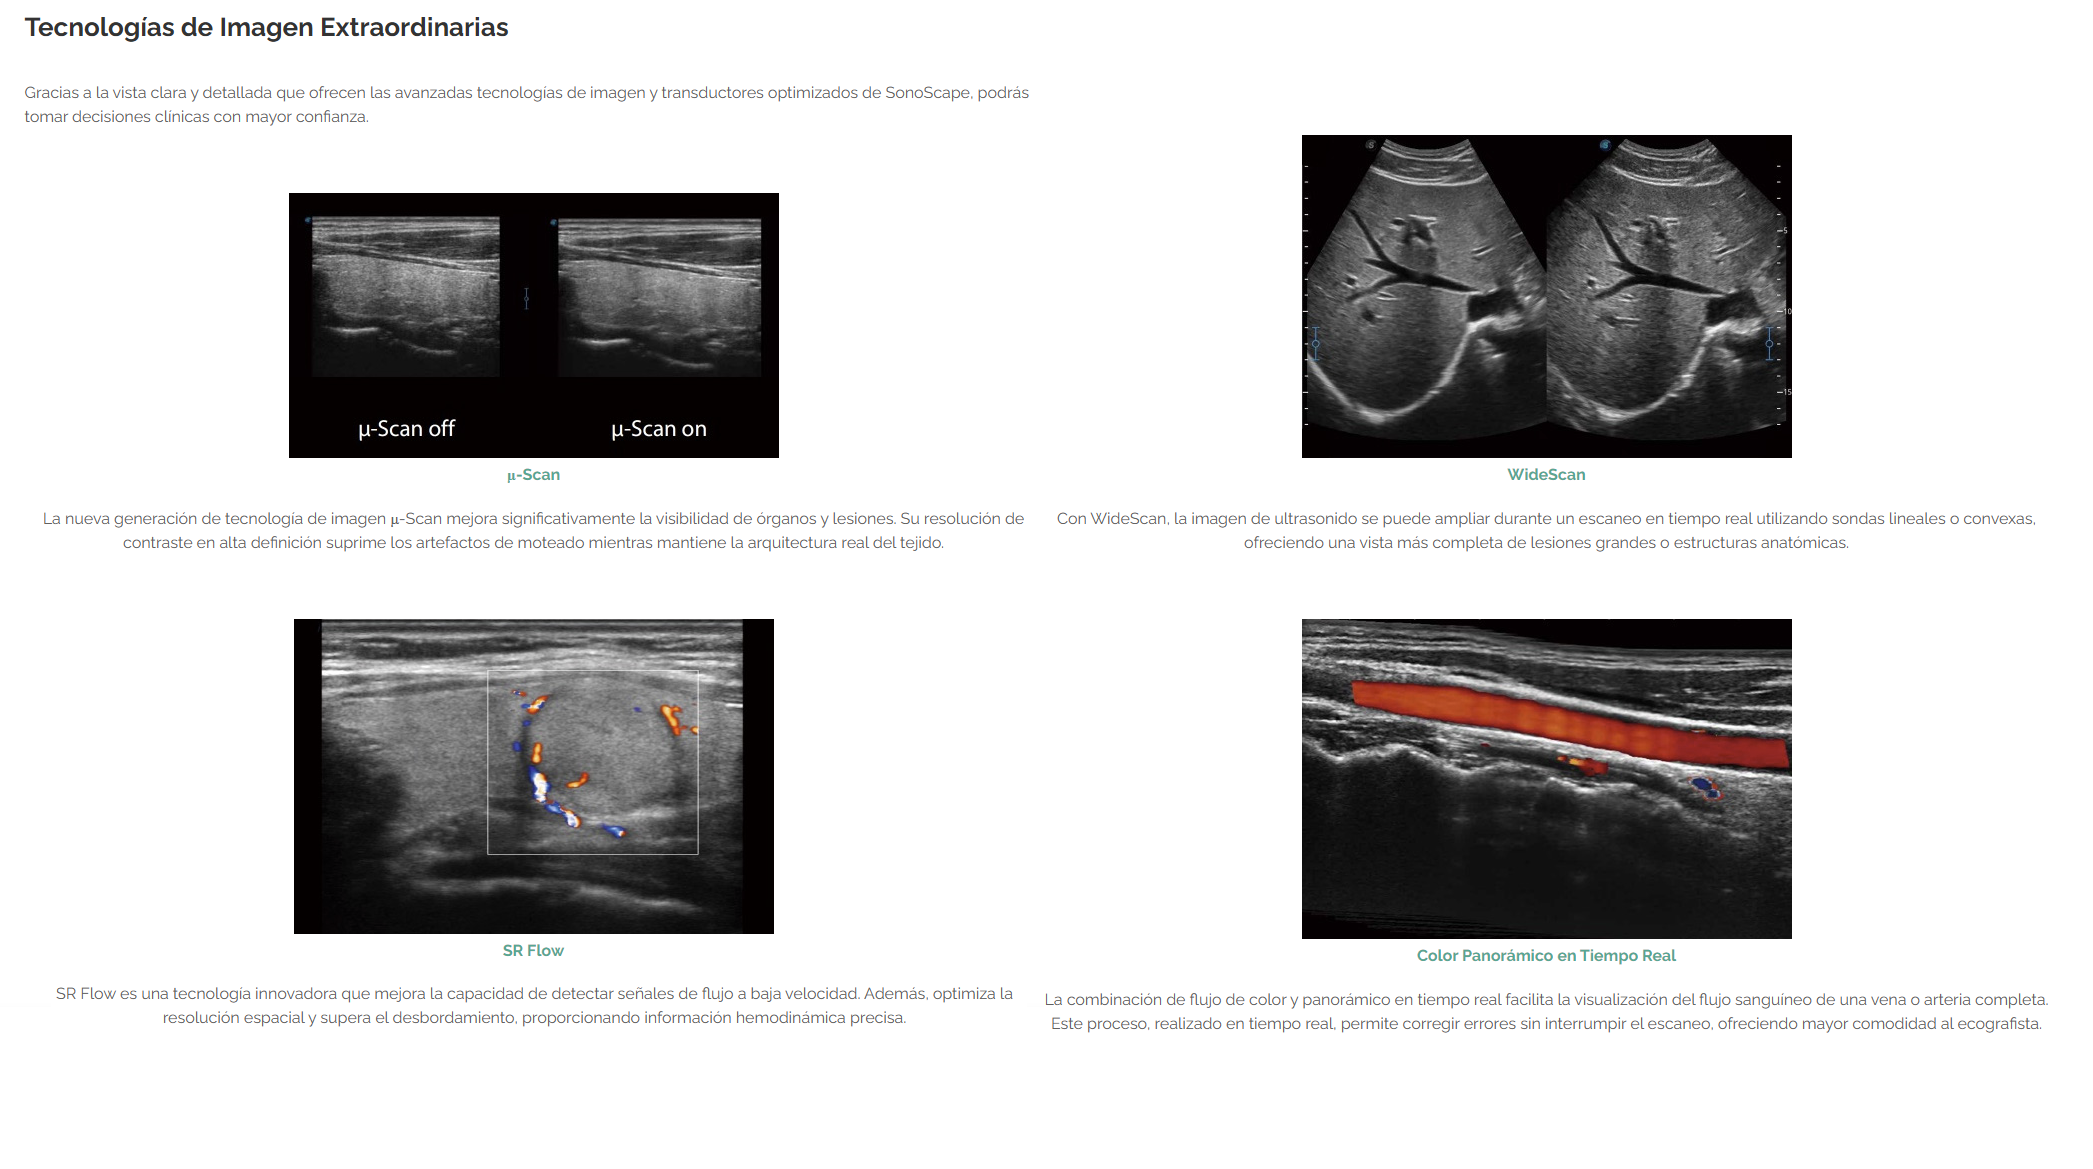

- Con la excelente visión clara proporcionada por las tecnologías de imágenes avanzadas de SonoScape y los transductores optimizados, puedes tomar decisiones clínicas con mayor confianza.

- SR Flow mejora la capacidad de detectar señales de flujo de baja velocidad.

- Con WideScan, la imagen de ultrasonido se puede ampliar cuando se realiza una exploración en tiempo real mediante el uso de sondas lineales o convexas.